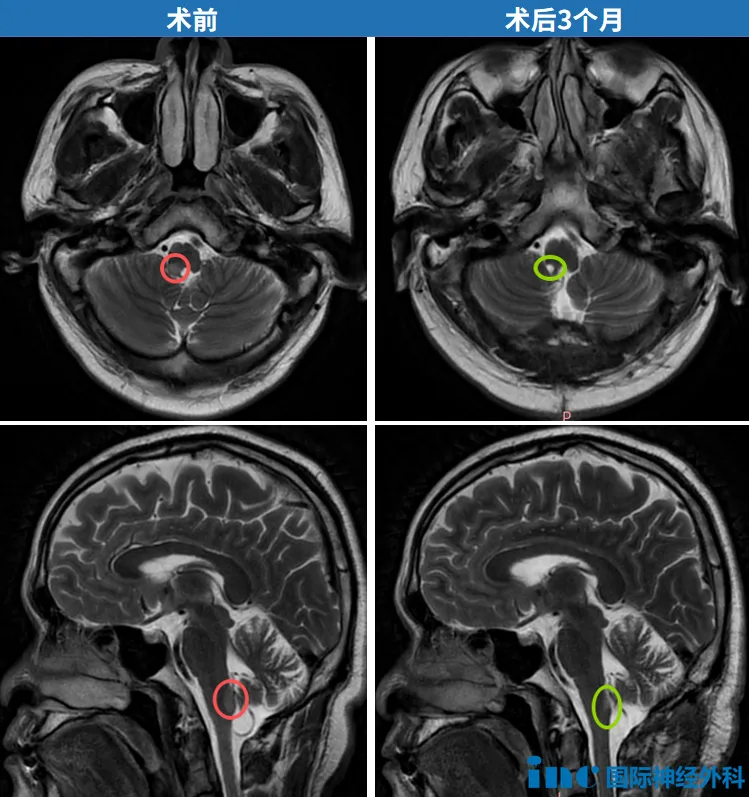

术后3个月复查影像显示肿瘤切除效果理想,脑干及周边结构保持完整。下次MRI复查可安排于8-9个月后。回归正常生活轨道的欧先生,特向巴教授咨询术后饮食限制事项。教授表示:“我认为无需进行饮食限制。”